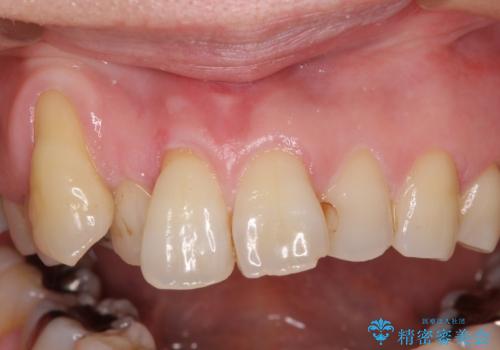

- 長年前歯の歯並びで悩んでいるとのことで来院された患者様です。

機能的なことを考えると八重歯となっている犬歯は抜歯せず、歯列を改善することが望ましいとされますが、数十年もの間犬歯がない咬み合わせで問題なく過ごしてきたため、八重歯を抜歯することで、手っ取り早く歯列を改善することとしました。

また、当初は予定しておりませんでしたが、歯列が整ったことで前歯の歯の色や形が気になり、矯正治療後にオールセラミッククラウンにて補綴治療することとしました。